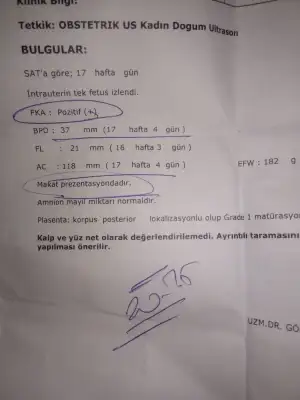

Notta perinatojiye yönlendirilmesi önerilir yazıyor.. İlk gebelikte hiç böyle bir şey ile karşılaşmamıştık. İnşaAllah bebeğim iyidir . Bir de erkek GİBİ. DEDİ. Ama 30.haftada bile değişkeni okudum.. Detaylı ultrasonu bekleyeyim ben gene de